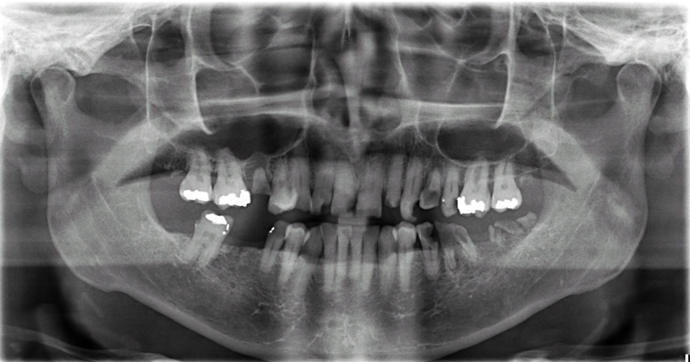

Patient had severe cavities throughout the mouth due to extreme dry mouth and history of use of tobacco. Patient was very discouraged as he had hated the idea of wearing dentures. Patient found Dr Bidra online and sought treatment and had all his teeth extracted and implants placed and new teeth installed all in 1 day! Patient was extremely satisfied with his transformation and eradication of all disease and bacterial infections.

Procedures : extractions, implants, All on 4 , Teeth in a day, no bone grafting and full mouth reconstruction with monolithic zirconia bridges.